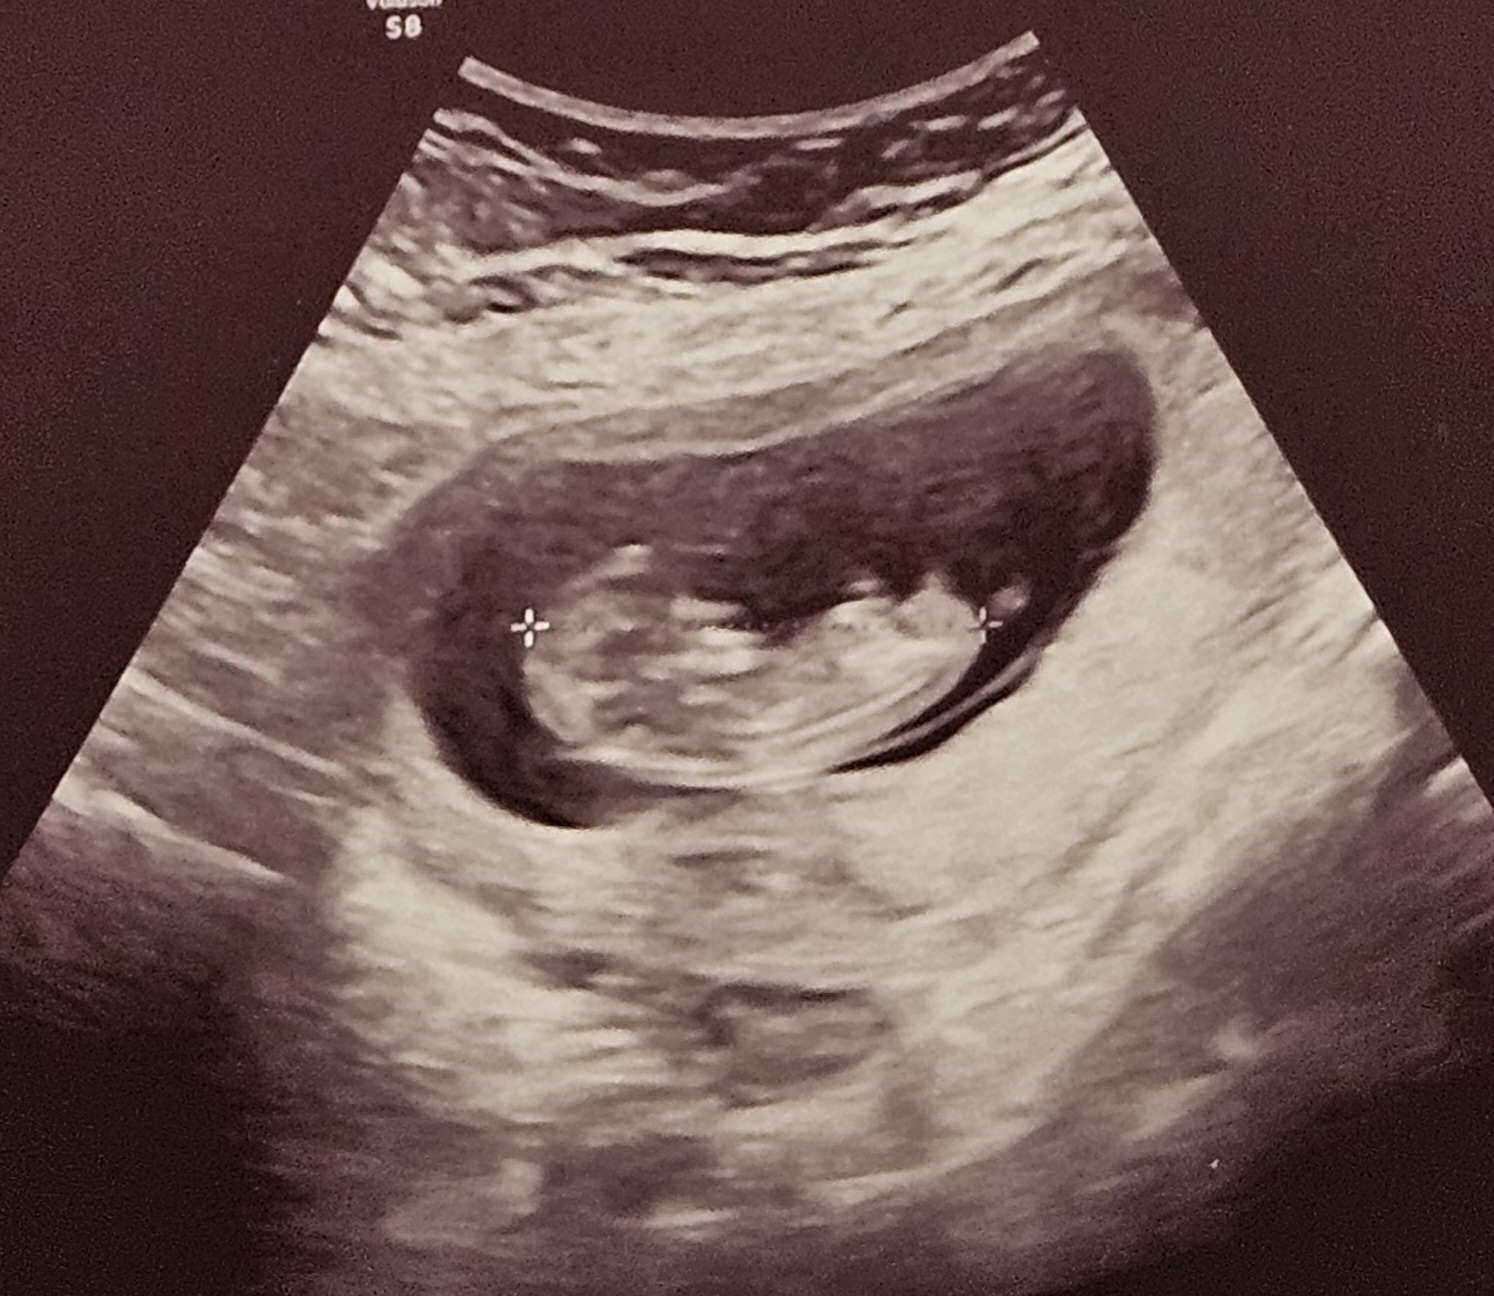

Ooo pokaż tego maluchaJa po wizycie, rusza się kluska. Ciśnienie miałam 155/99a w domu normalne. 4.5 cm już ma

ale wszystko było widać, nosek, nóżki, stópki, rączki, w szoku byłam że tak wyraźnie. Lepszy sprzęt ma babka niż mój ginekolog w pierwszej ciąży

Na żywo było lepiej widaćOoo pokaż tego malucha![]()